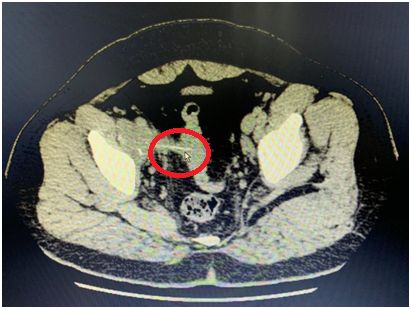

随后在CT和肠镜中,医生们惊奇地发现,李先生的盆腔里,有一个神秘的条!状!物!

它一头扎在肠内,另一头在肠外。

▲ CT内发现杆状物